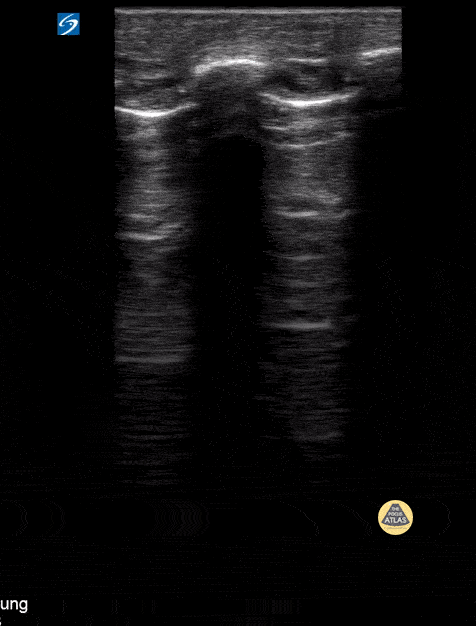

Lack of lung sliding. Contributor: Peter Gutierrez, MD, FAAP | Emory University School of Medicine/Children's Healthcare of Atlanta | @pocuspete